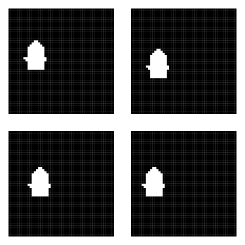

We again simulate a structure on a grid, displayed in Figure 4. Also displayed in the figure is one reliable candidate segmentation and three poor segmentations, the latter of which closely agree. We also simulate image intensities as might be obtained from an additional imaging modality. Voxelwise image intensity similarity is often used to quantify rater reliability throughout an image (Isgum et al., 2009). As such, we simulate image intensity similarities for each atlas, displayed in Supplementary Figure 1. To make the assessment more realistic, we slightly offset the intensity differences from the areas of poor segmentations.

Most existing label fusion procedures result in a binary map corresponding to inclusion/exclusion of voxels in a structure of interest. Thresholding the posterior probability maps at 0.5 also yields such a binary map, displayed in Figure 6. For comparison, the figure also displays the segmentations that result from simple majority voting, globally-weighted majority voting (Artaechevarria et al., 2008) in which each atlas is weighted by the inverse of its average squared intensity difference, and locally-weighted majority voting (Artaechevarria et al., 2009) in which the contribution of each atlas at each pixel is weighted by the inverse squared intensity difference from the target. We can see the superior recovery of the target under our approach versus different versions of majority voting. The figure also gives the Dice similarity coefficients quantifying similarity between each segmentation and the target, where the target is dichotomized to zero / non-zero pixels. Let denote the indicator of inclusion of pixel in the estimated image. The Dice coefficient, calculated as , is often used as a measure of image similarity (though it may not be the best measure when the structure of interest is small relative to the image size (Taha and Hanbury, 2015)). Dice values close to one indicate strong agreement between two images. Despite the fact that all of the poor segmentations were downweighted relative to the good one, they still outweigh the quality atlas in each voting procedure, resulting in poor segmentation. Thresholding the posterior probability map has resulted in improvement in similarity over even the most favorable version of majority voting.

Often, a researcher is uninterested in a binary segmentation for its own sake, but rather as a means to an end; e.g., volume estimation. With a binary segmentation, the only way to estimate the volume is by summing the binary indicators over the image. In contrast, our approach facilitates construction of a distribution of plausible volumes. Let denote the realization of on iteration of the MCMC output. Recognizing that , we estimate the structure volume on iteration with . The right panel in Figure 6 displays the estimated marginal distribution of volume, along with the true volume and the volume estimates obtained from the three voting procedures. The true volume is well within the high probability region of the distribution. We have no way of formally quantifying the uncertainty associated with the voting estimates.